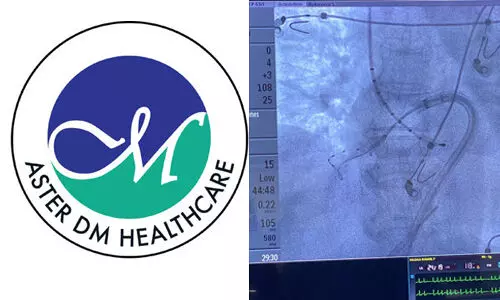

കൊച്ചി:ഹൃദ്രോഗ ചികില്സയില് ക്രയോഅബ്ലേഷന് നൂതന ചികില്സാസംവിധാനമൊരുക്കി ആസ്റ്റര് മെഡ്സിറ്റി.ക്രയോഅബ്ലേഷന് എന്ന പദം രൂപപ്പെടുന്നത് 'ക്രയോ' എന്നര്Lം വരുന്ന തണുപ്പ് എന്നും നീക്കം ചെയ്യല് എന്നര്Lം വരുന്ന 'അബ്ലേഷന് 'എന്നും രണ്ട് പദങ്ങള് ചേര്ന്നാണ്. പക്ഷാഘാതത്തിനും മറ്റ് ഹൃദയതകരാറുകള്ക്കും കാരണമാകുന്ന അസാധാരണമായ വൈദ്യുത പാതകളെ തടസ്സപ്പെടുത്തിയതിന് ശേഷം സാധാരണ നിലയിലുള്ള ഹൃദയമിടിപ്പ് പുനഃസ്ഥാപിക്കാന് സഹായിക്കുന്ന ഏറ്റവും നൂതനവും വിജയകരവുമായ പ്രക്രിയയാണ് ബലൂണ് ക്രയോഅബ്ലേഷന് എന്ന് ആസ്റ്റര് മെഡ് സിറ്റി അധികൃതര് വ്യക്തമാക്കി.

രോഗിയുടെ കാലിലെ രക്തധമനിയിലൂടെ കടത്തിവിടുന്ന കത്തീറ്റര് നൂതന ഇമേജിംഗ് സാങ്കേതികവിദ്യ ഉപയോഗിച്ച് ഹൃദയത്തിലേക്ക് നയിക്കപ്പെടുന്നു. സാധാരണയില് നിന്ന് വിപരീതമായി നൈട്രസ് ഓക്സൈഡ് വാതകത്തിന്റെ സഹായത്താല് രക്തം കട്ടപിടിച്ചിരിക്കുന്ന ഭാഗം തണുപ്പിക്കുന്നു. കുറഞ്ഞ താപനിലയില് തന്നെ ബലൂണിന്റെ സഹായത്താല് പ്രക്രിയ പൂര്ത്തിയാക്കുന്നതിനാല് മറ്റ് കോശങ്ങള്ക്ക് നാശം സംഭവിക്കുന്നില്ല എന്നതാണ് ഈ ചികിത്സാരീതിയുടെ ഗുണം. പ്രക്രിയ പൂര്ത്തിയാക്കി തൊട്ടടുത്ത ദിവസം തന്നെ രോഗിക്ക് വീട്ടിലേക്ക് മടങ്ങാനുമാകും.